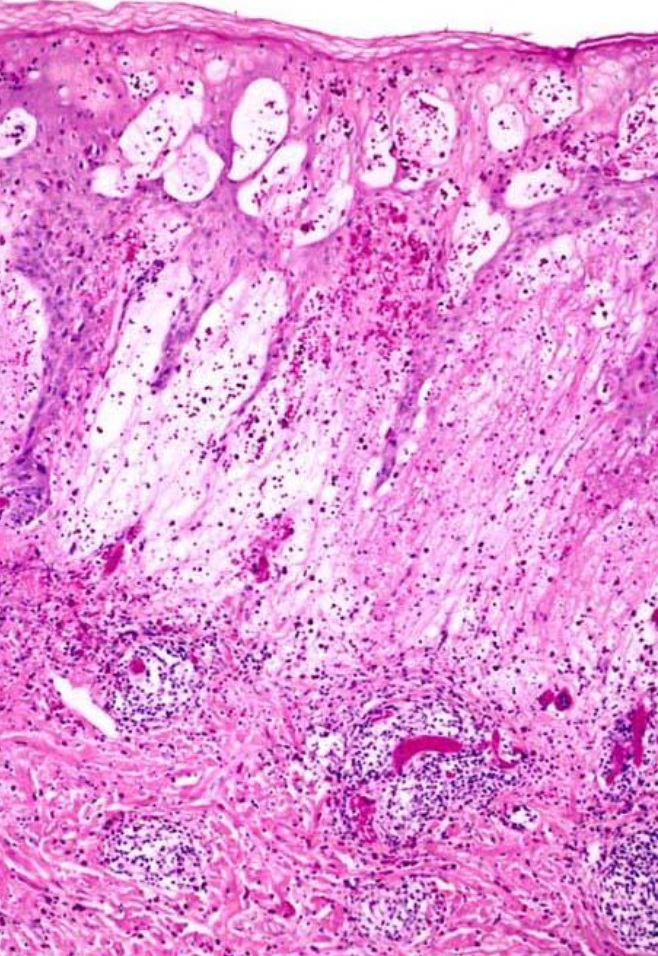

5

A

Acute Eczematous Dermatitis

Edema/fluid, splays apart keratinocytes → spongiotic dermatitis